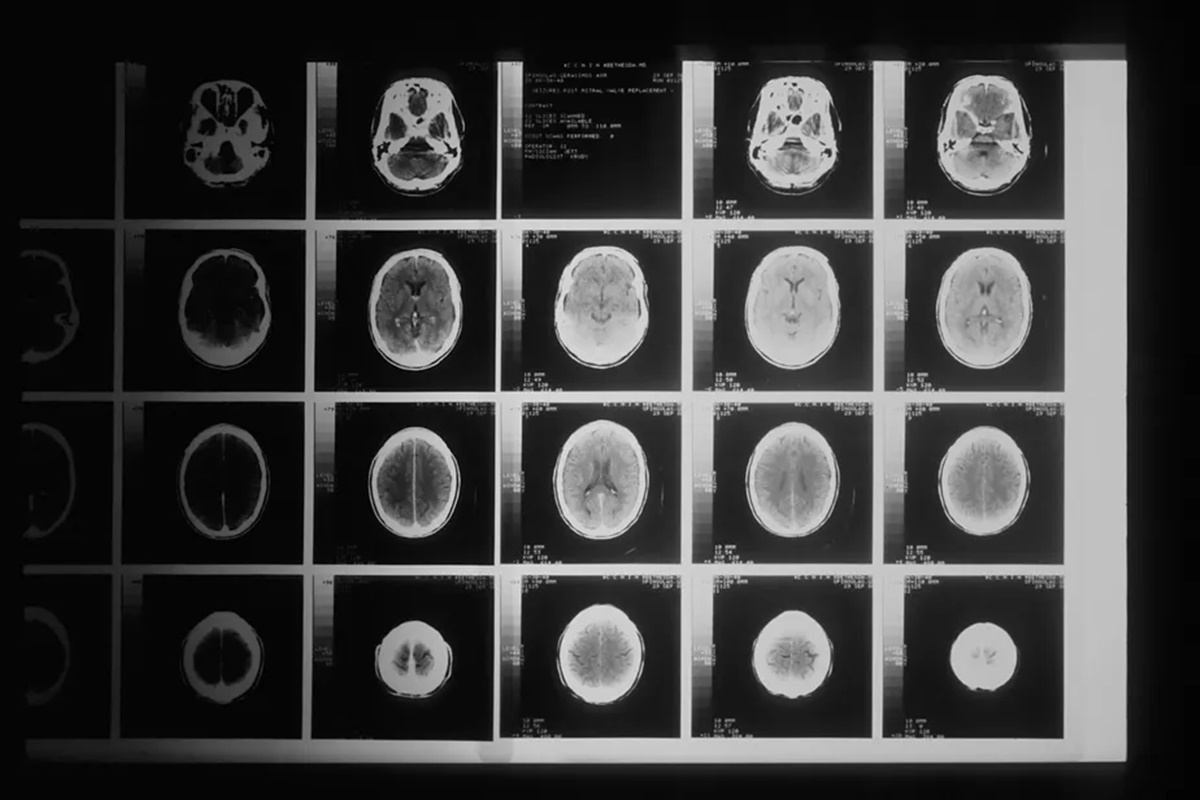

Os cérebros dos adolescentes que passaram por lockdowns durante a pandemia de Covid-19 mostram sinais de envelhecimento prematuro, de acordo com um estudo publicado na revista científica Biological Psychiatry: Global Open Science. Os pesquisadores também observaram pior saúde mental, mas não está claro se isso está ligado à diferença de idade do cérebro.

A equipe da Universidade de Stanford, nos Estados Unidos, analisou exames de ressonância magnética de 81 adolescentes nos EUA feitos antes da pandemia, com os de outros 82 adolescentes feitos entre outubro de 2020 e março de 2022, durante a pandemia, mas depois que os lockdowns foram suspensos.

Depois de combinar 64 participantes de cada grupo por fatores como idade e sexo, a equipe descobriu que as mudanças físicas no cérebro que ocorreram durante a adolescência – como o afinamento do córtex e o crescimento do hipocampo e da amígdala – foram maiores no período pós-lockdown do que no pré-pandemia. Isso indica que seus cérebros envelheceram mais rápido.